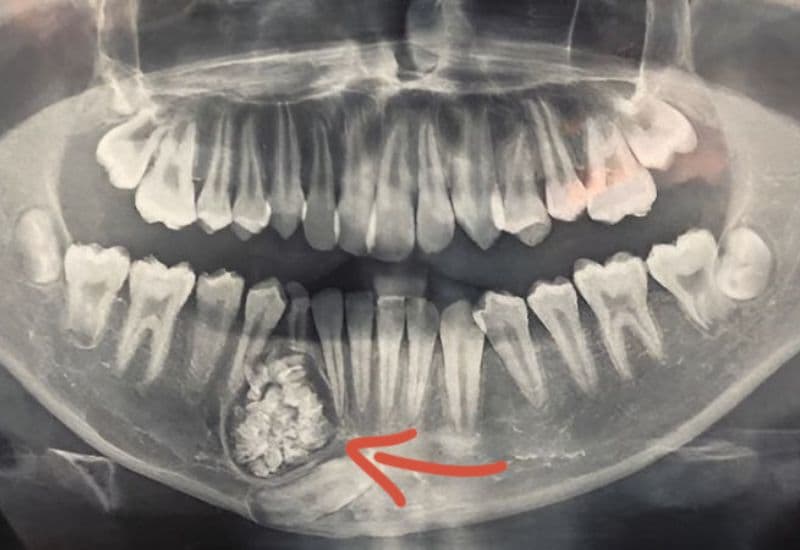

U chân răng là một trong những bệnh lý răng miệng có thể tiến triển âm thầm nhưng gây ảnh hưởng đáng kể nếu không được phát hiện sớm. Nhiều người chỉ biết đến tình trạng này khi xuất hiện sưng đau, nhiễm trùng hoặc tình cờ phát hiện qua chụp X-quang nha khoa. Vậy u chân răng là bệnh gì, vì sao lại hình thành và có nguy hiểm không?

U chân răng là tình trạng tổn thương dạng khối xuất hiện ở vùng quanh chân răng, thường liên quan đến các mô răng hoặc mô nướu phát triển bất thường. Trong đa số trường hợp, đây là u lành tính, tiến triển chậm và hình thành do sự rối loạn trong quá trình phát triển mô răng hoặc do viêm nhiễm kéo dài không được xử lý triệt để.

Đây là loại phổ biến nhất, hình thành do viêm nhiễm kéo dài ở vùng chóp răng, thường gặp ở răng đã chết tủy hoặc răng sâu nặng. Khối u phát triển chậm và thường chỉ được phát hiện tình cờ khi chụp X-quang. - U nang thân răng